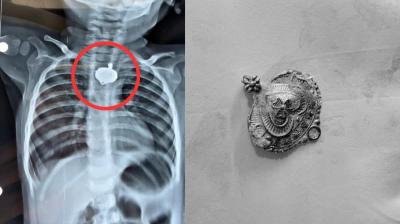

बड़वानी में 9 माह के बच्चे की आहार नली में फंसा मंगलसूत्र, डेढ़ महीने बाद एक्स-रे से खुलासा

24 Nov, 2025 08:30 AM IST | JAGATVISION.CO.IN

बड़वानी: रविवार को जिला अस्पताल में एक बेहद संवेदनशील और हैरान करने वाला मामला सामने आया. जब 9 माह के एक बच्चे के गले में मंगलसूत्र फंसा हुआ देखा गया. घटना...